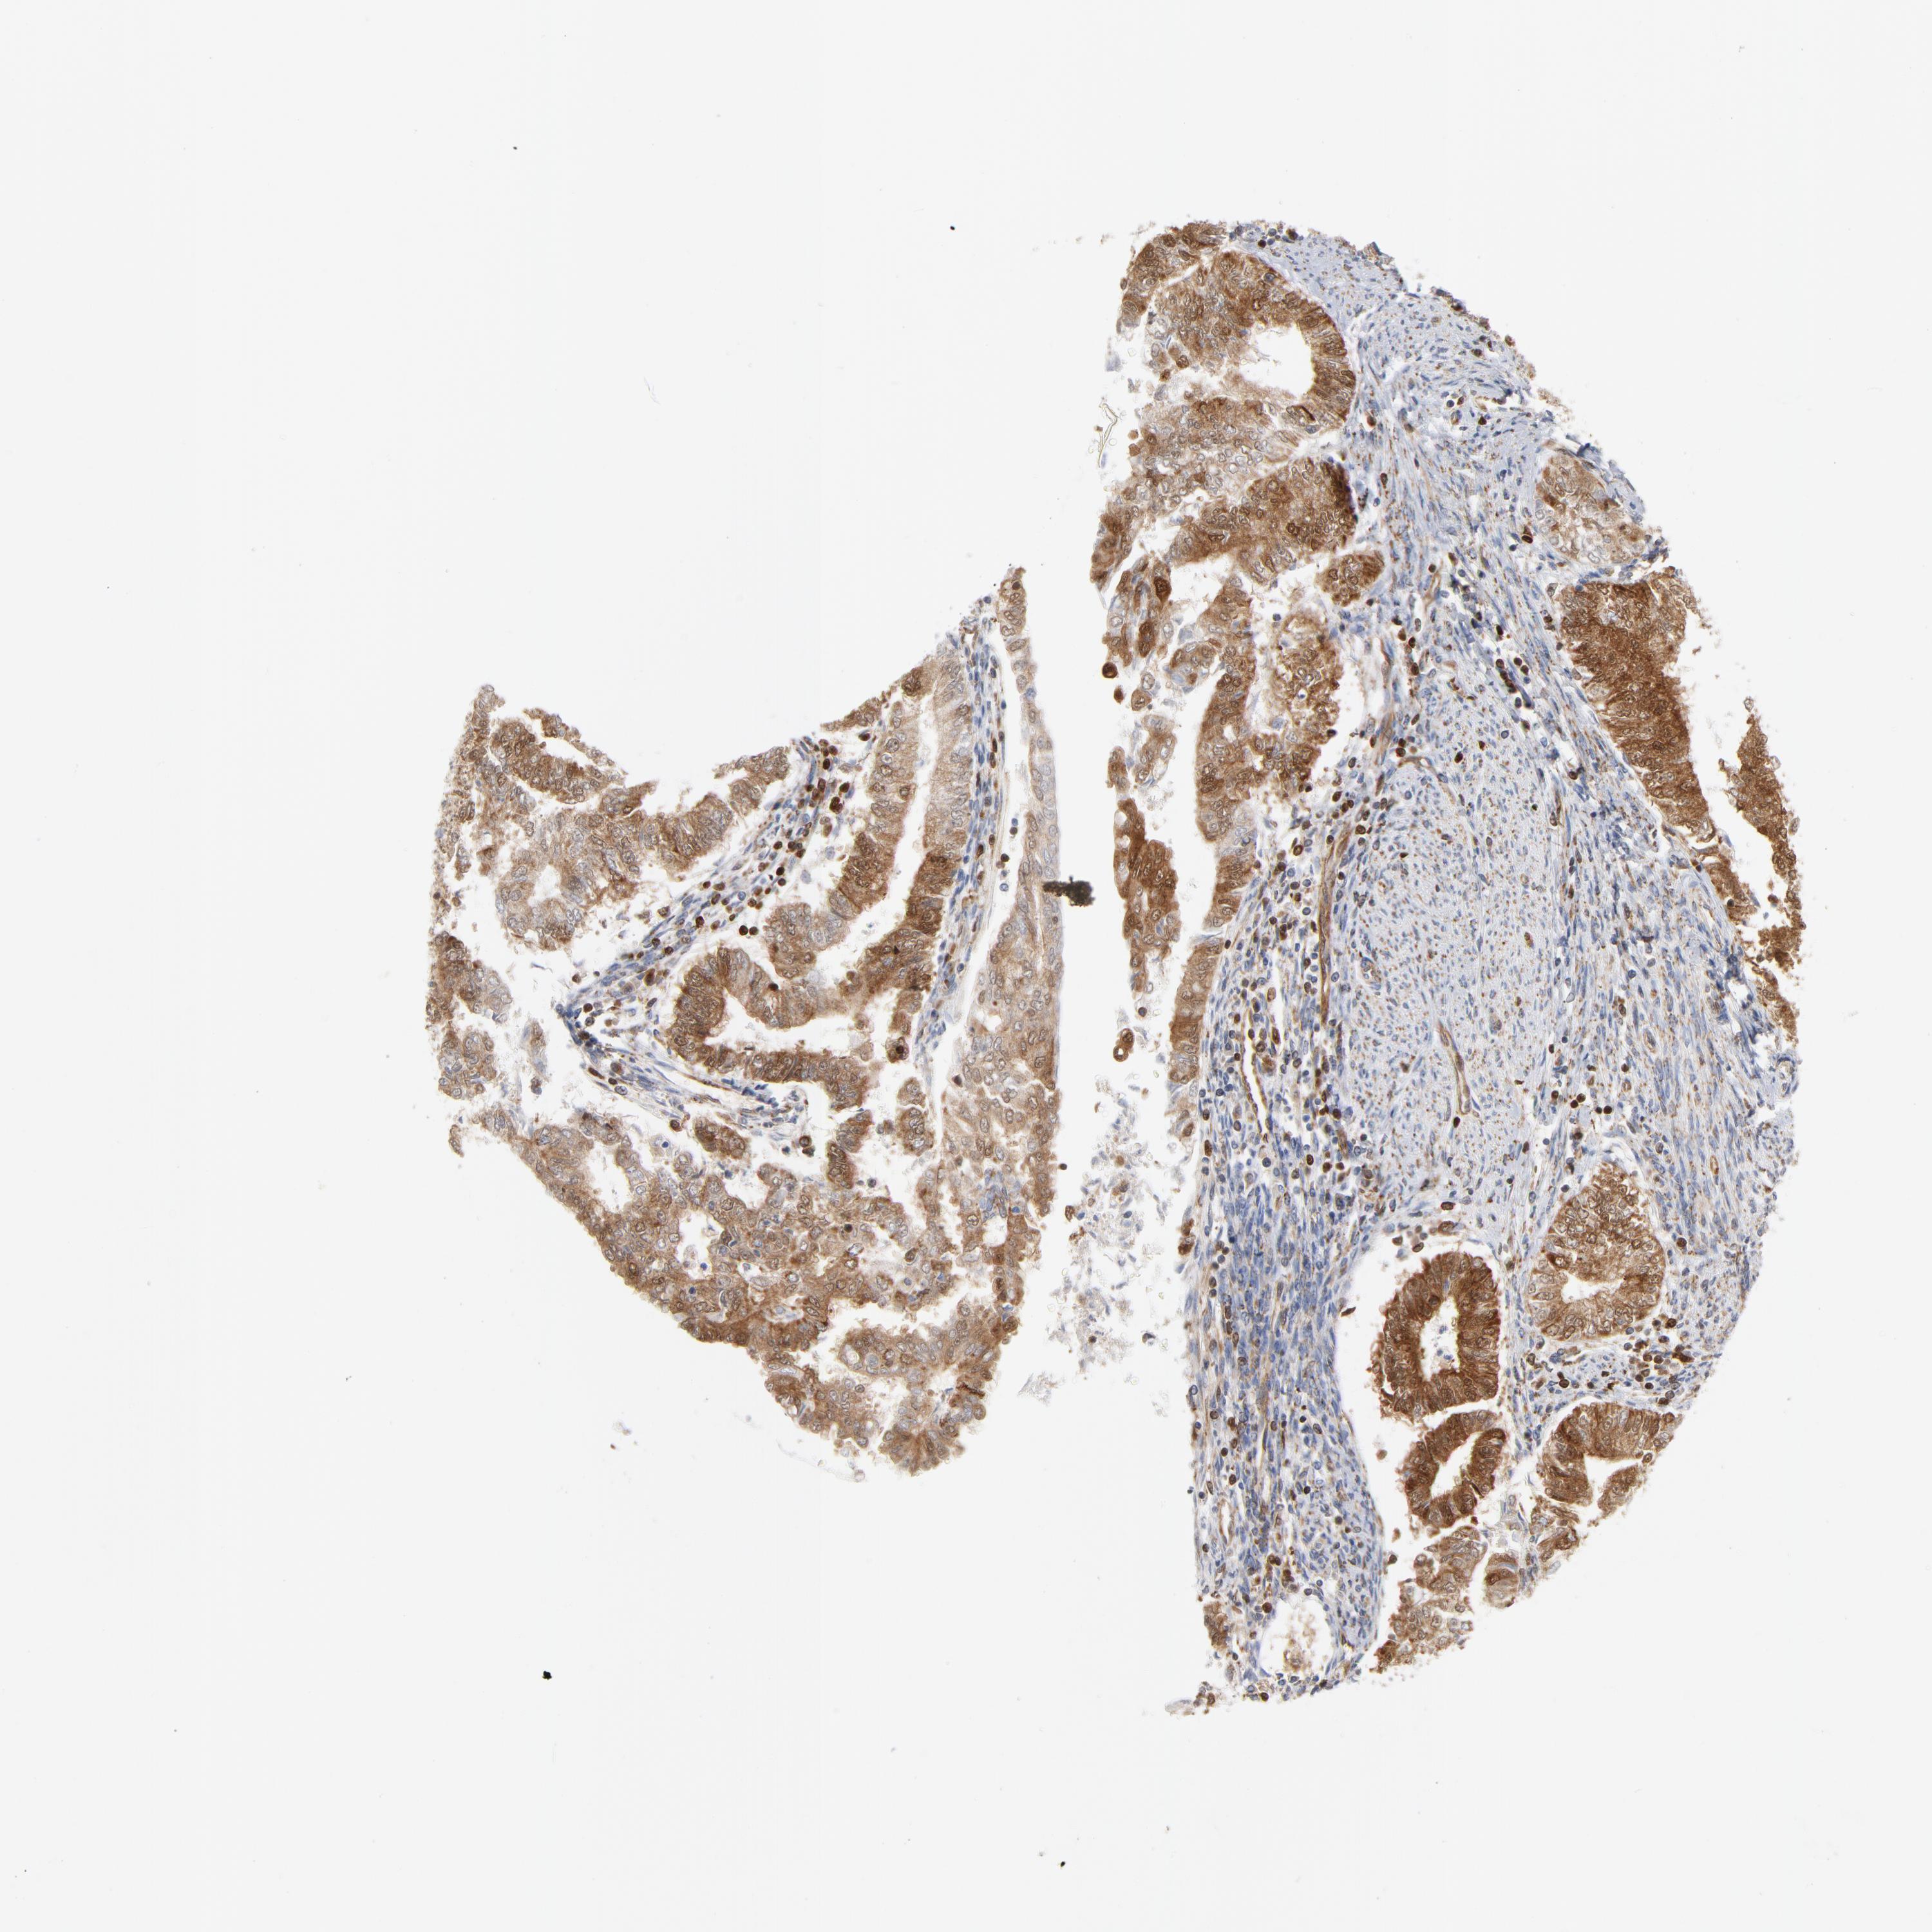

ENDOMETRIAL CANCER - Protein expressioni

A mouse-over function shows sample information and annotation data. Click on an image to view it in a full screen mode. Samples can be filtered based on level of antibody staining by selecting one or several of the following categories: high, medium, low and not detected. The assay and annotation is described here.

Note that samples used for immunohistochemistry by the Human Protein Atlas do not correspond to samples in the TCGA dataset.

Antibody stainingi

Antibody staining in the annotated cell types in the current human tissue is reported as not detected, low, medium, or high, based on conventional immunohistochemistry profiling in selected tissues. This score is based on the combination of the staining intensity and fraction of stained cells.

Each image is clickable and will lead to virtual microscopy that enables deeper exploration of all samples and also displays staining intensity scores, fraction scores and subcellular localization as well as patient and tissue information for each sample.

Antibody HPA001825

Antibody CAB003857

Staining

High

Medium

Low

Not detected

Intensity

Strong

Moderate

Weak

Negative

Quantity

>75%

75%-25%

<25%

None

Location

Nuclear

Cytoplasmic/membranous

Cytoplasmic/membranous,nuclear

Adenocarcinoma, NOS

Neoplasm, malignant, NOS